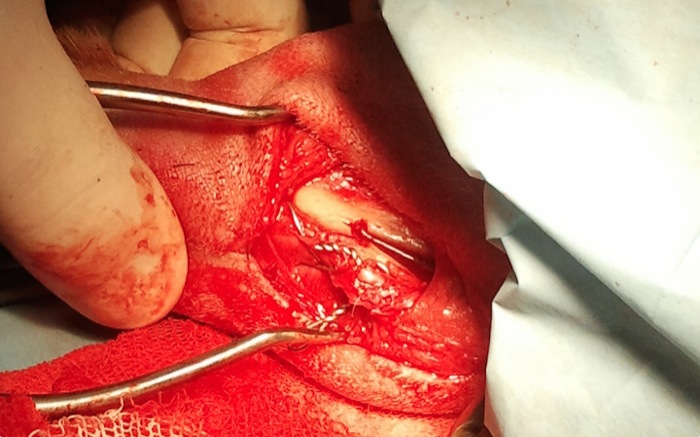

Tras una capsulorrafia lateral estándar eliminamos el ligamento cruzado roto y lavamos con suero. En este caso se realiza también una liberación de menisco medial mediante una miniartrotomía medial. La artrotomía se cerrará y continúa la cirugía a nivel de la cresta tibial desperiostizando minimamente la linea de corte.

Se coloca un cerclaje en ocho que es tensado a cada lado para asegurar la cresta ante la fuerza hacia proximal del sistema del cuádriceps. Son frecuentes las fracturas distales de la cresta al abrir el espacio para la celdilla pero no es un problema dado que el periostio sigue intacto y tenemos el cerclaje de seguridad.

Se cierra la osteotomía, hecha con sierra oscilante y sin guía, tras la colocación en proximal de la celda de 6 mm sujeta con 2 tornillos de 2,7 mm colocados de medial a lateral y algo separados del corte.